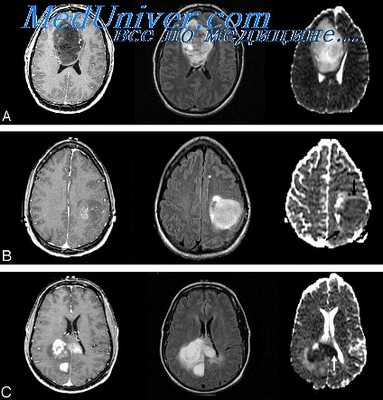

(а) МРТ, Т2-ВИ SPACE, аксиальный срез: у мужчины 57 лет со шванномой в области правого мостомозжечкового угла определяется гетерогенно гипоинтенсивное объемное образование, распространяющееся вплотную к яремному отверстию.

(б) Отмечается интенсивное контрастирование образования по типу мишени, что является признаком шванномы. Учитывая локализацию и распространение, опухоль может развиваться из ЧН IX, X, XI. Центральная область, не накапливающая контраст, соответствует участку гиперинтенсивного на Т2-ВИ (не представлены) сигнала, что часто наблюдается в областях Антони В с гипоцеллюлярностью и миксоидной стромой.